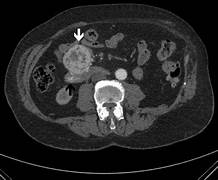

Imaging studies (ultrasound, CT scan, MRI)

Ultrasonography, computed tomography, and magnetic resonance cholangiopancreatography are three noninvasive imaging techniques for people with jaundice. Ultrasonography or computed tomography is typically the first-line option for evaluating blockage, cirrhosis, and vascular patency, with ultrasonography being the least intrusive and most cost-effective method. Magnetic resonance cholangiopancreatography or endoscopic retrograde cholangio- pancreatography can be used to see the intra- and extrahepatic biliary tree further, with the latter allowing for treatment options such as biliary stent implantation to ease blockage. Endoscopic ultrasonography, in conjunction with endoscopic retrograde cholangiopancreato- graphy, can evaluate common bile duct blockages and distinguish between a mass and a stone.

Fig 1. Ct Scan